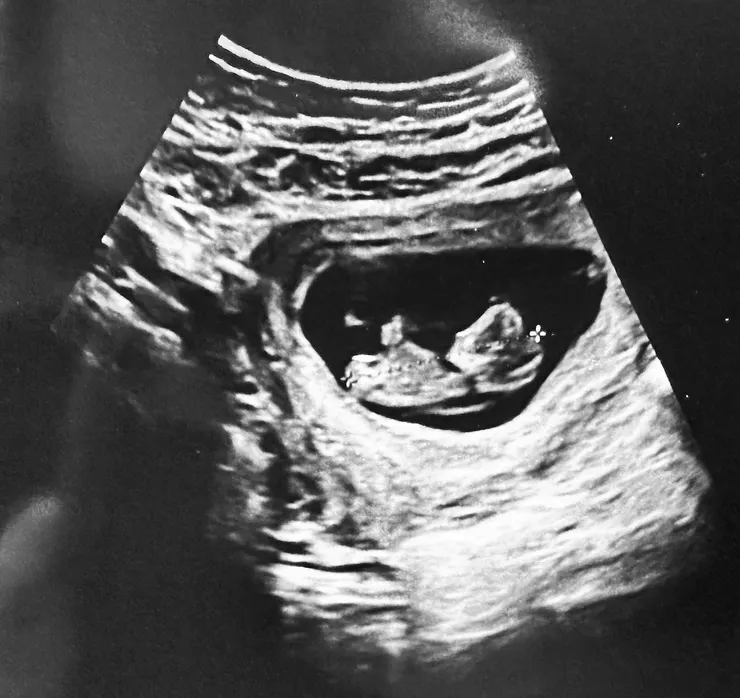

10w+4d,比起上次8w的肉團,已經看得出頭跟鼻子啦!